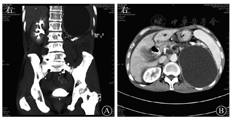

血常规WBC计数为2.74×109/L,RBC计数为3.12×1012/L,PLT计数为84×109/L。血清淀粉酶为112 U/L,胆红素水平正常。肿瘤标志物:AFP正常,CEA为11.07 μg/L,CA19-9为205.50 kU/L,CA125为116.90 kU/L。HBsAg为172.62 mIU/mL,其他乙型肝炎标志物均正常。2016年6月24日,上腹部CT平扫和增强(图1)示:①胆系扩张,胆总管下段有软组织密度影并强化,需考虑占位可能;②胆总管下段多发结石;③慢性胰腺炎并胰管明显扩张;④胆囊结石并胆囊炎;⑤肝硬化;⑥左肾结石,左肾巨大囊肿。MRI和MRCP检查(图2)示:①胆总管下段结石并胆系扩张;②胆总管下段狭窄,需排除占位;③左肾区巨大囊肿。7月2日行内镜下逆行胰胆管造影术(endoscopic retrograde cholangiopancreatography,ERCP),内镜显示食管静脉曲张(重度),胆管造影示胆总管中段明显狭窄,狭窄处长约2.0 cm,狭窄以上肝外胆管扩张,术中胆管腔内超声(intraductal ultrasonography,IDUS)检查狭窄处胆管未见明显异常,造影未见明确结石影,沿胆总管导丝置入覆膜金属支架于狭窄处。7月7日泌尿系统多普勒超声检查示左肾窝异常回声团块,考虑左肾囊肿可能。7月9日计算机断层扫描泌尿系统延时成像(computed tomographic urography,CTU)(图3)示:左肾区囊性病灶未见造影剂进入,提示假性囊肿形成可能性大。7月20日肝脏静脉血管造影(computed tomographic venography,CTV)(图4)示:肠系膜上静脉血栓形成,门静脉主干起始处闭塞,门静脉海绵样变性。8月1日复查CT增强(图5)示:①肝内胆管扩张、胆总管内置管术后改变。②慢性胰腺炎;胰尾囊肿引流术后,囊腔内积气。

泌尿外科张成主治医师:患者上腹部CT平扫和增强显示左肾结石;左肾实质见一巨大无强化囊性占位,由于囊肿与肾实质无显著分界,首先要考虑左肾巨大囊肿,其次囊肿与胰尾也紧密相连,与胰腺假性囊肿难以鉴别。建议完善左侧逆行肾盂造影或CTU,若明确诊断为左肾囊肿后,可转泌尿外科进行手术治疗。

影像科何来昌副主任医师:CT和MRI检查均提示左侧中上腹部巨大囊肿性肿块,胰体尾部、脾脏和脾血管均向前移位,提示囊性病变位于左侧腹膜后间隙内,而腹膜后间隙内实质性器官包括胰腺、肾脏和肾上腺,需要对这些脏器来源的囊性病变进行逐一排除。结合患者的临床表现,影像学检查有慢性胰腺炎的特征性表现,确实需考虑胰腺假性囊肿的可能。然而影像学图像上可见左侧肾上腺完整并轻度上移,左肾中上部肾实质萎缩,左肾整体轻度下移,囊肿与左肾实质分界不清,而与胰腺分界较为清晰,故还要考虑囊性病变为左肾来源的可能性。左肾来源的囊性病变主要包括肾囊肿,囊性肾癌,肾盂、肾盏囊性扩张积水。其中,肾囊肿包括单纯性肾囊肿和复杂性肾囊肿。单纯性肾囊肿的影像学表现为肾实质内边缘光整、锐利,囊壁菲薄且无强化的囊性占位,囊液呈水样密度或信号影,增强亦无强化。复杂性肾囊肿是单纯肾囊肿合并出血或感染等炎性反应刺激,可使局部机化、钙化、血管及肉芽肿形成,其囊壁通常增厚,囊液成分复杂,其影像学表现也较为多变,可于囊内或囊壁出现钙化,囊内液体可因含有蛋白质、黏液成分而呈现较高的密度和磁共振序列上的复杂信号,囊内多无分隔和壁结节影,其囊壁可有强化,而囊内液体则无明显强化。囊性肾癌则多可见强化的囊壁、囊内分隔和壁结节影[7]。肾盂、肾盏囊性扩张积水多为肾结石或炎性反应继发,影像学检查可发现原发病变,CTU检查多可见造影剂进入囊性扩张的肾盂、肾盏内。本例患者CT和MRI检查均提示囊性病灶囊壁较厚、囊壁钙化,囊内未发现明确的分隔和壁结节,囊液密度较高且弥散受限,增强扫描囊壁轻度强化,然而CTU检查未见造影剂进入囊性病灶内,故考虑复杂性肾囊肿的可能性大。目前,从影像学检查上尚难确诊是胰腺假性囊肿还是左肾囊肿,建议穿刺检测分析囊内成分,可进一步将其与胰腺假性囊肿进行鉴别。

泌尿外科钟柯兆副主任医师:患者CTU检查见左侧腹膜后间隙巨大囊肿毗邻左肾和胰尾部,囊壁厚、轻度强化,左肾盂、肾盏显影不良,不考虑左肾囊肿,而应考虑胰腺假性囊肿。左侧腹膜后间隙较狭窄,这一部位出现胰腺假性囊肿易误诊为左肾囊肿,以往泌尿外科曾有几例类似病例,在手术中发现并非左肾囊肿,而是胰腺假性囊肿。该例患者不考虑左肾囊肿的理由:首先,肾囊肿的囊壁一般很薄,而该例患者的囊壁厚,囊壁应属于胰腺炎性反应后纤维结缔组织增生包裹所致;其次,CTU示无造影剂进入囊内,说明囊液与泌尿系统不相通;最后,囊性病变虽与左肾分界不清,但是通过仔细阅片,左肾实质更似压迫萎缩改变。同意消化科的诊治意见,在多普勒超声引导下进行诊断性穿刺,检测穿刺液的肌酐和淀粉酶水平,必要时可进一步行引流治疗。